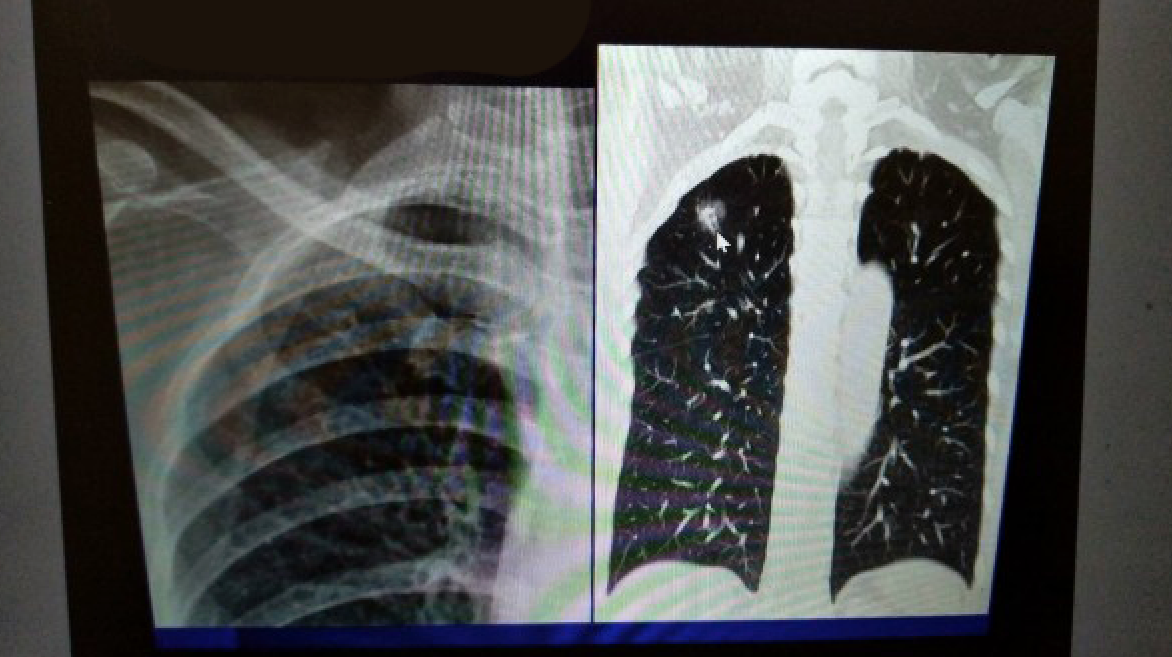

2019年01月24日你可知道「肺部問題」是影響最多台灣人的身體問題第一名嗎?根據衛福部統計,受影響的女性居然比男性更多,但是奇怪的是,患者之中卻有高達8成的女性不碰菸。醫師認為這可能跟空汙、二手菸和油煙比較有關係,甚至警告大家「煮一頓飯就等於抽2包菸」,必須靠一個習慣來保命!

▼根據近年的數據來看,女性患者的增加速度非常快,10年來一直居高不下。根據國外研究指出,就算一個人沒有碰菸的習慣,空氣污染也是造成身體出狀況的原因之一,佔了2至3成。